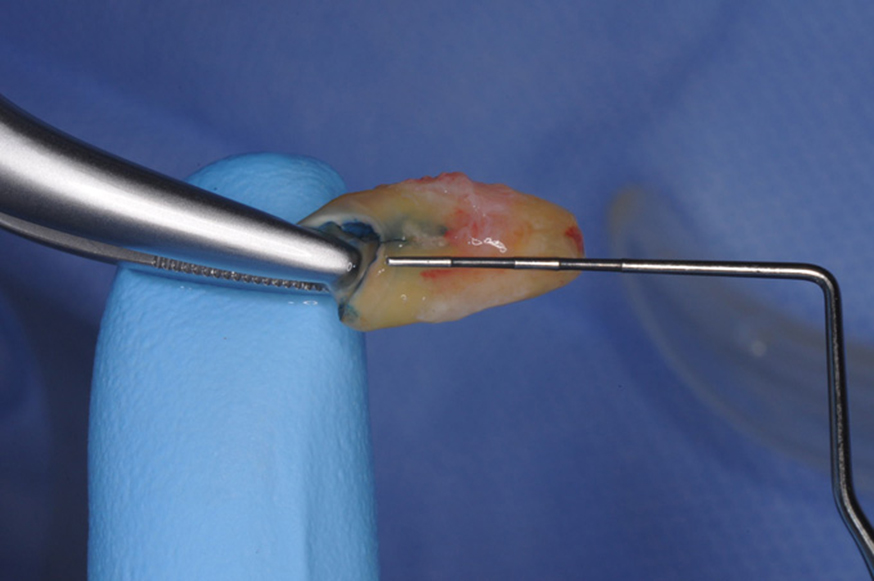

図7 予後不良歯根の抜歯

口蓋根の破折は約3㎜です。歯根長は10㎜なので意図的再植(抜いた歯を治療して再度元の場所に戻す方法)は見送りました。

残った2つの歯根は感染根管治療とルートプレーニングを行って、ポストコアを再製し仮歯で歯肉の治癒を待ちます。